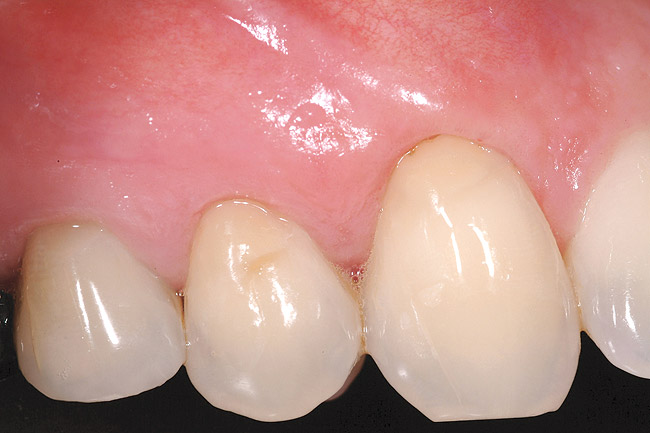

Figure 20  Case Two Case Two, complete view.

Figure 20

Figure 20 shows the completed view with the final restoration seated. Observe the balance of the facial heights of contour between the central incisors, and the presence of a thick-biotype, attached keratinized tissue.